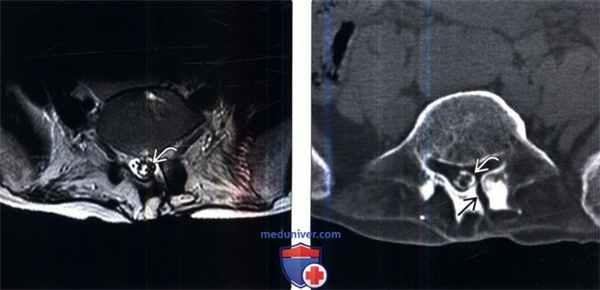

(Слева) Сагиттальный срез, Т2-ВИ поясничного отдела позвоночника: зоны гипоинтенсивного сигнала вдоль границ каудальной части дурального мешка, являющиеся проявлениями кальцифицирующего арахноидита.

(Справа) Сагиттальный КТ-срез, этот же пациент: хорошо видны грубые кальцинаты дистальной части дурального мешка. Также определяются признаки межтелового костного блока на уровне L3-L4, L4-L5 и L5-S1.

(Слева) Аксиальный срез, Т2-ВИ: зона гипоинтенсивного сигнала в области границ дурального мешка представляющая собой кальцинаты.

(Справа) Аксиальный КТ-срез: грубые кальцинаты каудальной части дурального мешка. Также здесь визуализируется послеоперационный дефект в левой пластинке дуг и L5.